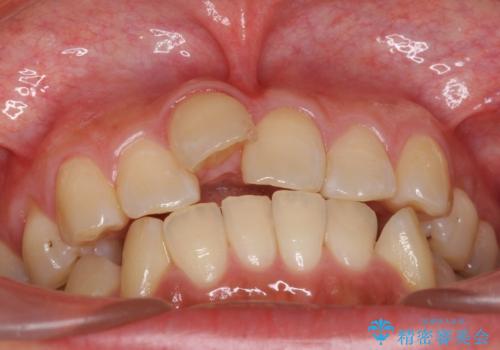

前歯を引っ込めたい 歯を抜かずにマウスピースで

- 20代女性

- インビザライン

- 1年11ヶ月

- 前歯の突出を主訴に来院。

上の奥歯を後ろに下げて治療をしました。

矯正用のミニスクリューを使用しています。

上の前歯もIPR(エナメル質をわずかに削る処置)を行っています。